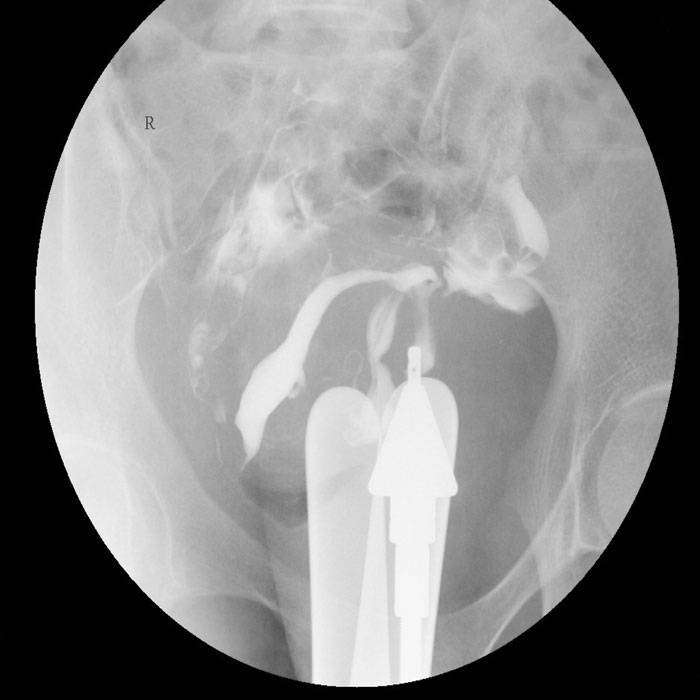

Histerosalpingografi, ilaçlı rahim ve tüp filmi anlamına gelmektedir. Rahim içinin, rahim ağzı kanalının ve fallop tüplerin işlevsel ve yapısal özelliklerini incelemede kullanılan bir yöntemdir. Rahim içine özel bir sıvı verilerek, bu yapıların görüntülenmesi sağlanır. Histerosalpingografi genel olarak rahim içindeki yapışıklıktan, rahim ağzı kanalındaki veya fallop tüplerindeki bir tıkanıklıktan şüphelenildiğinde uygulanır.